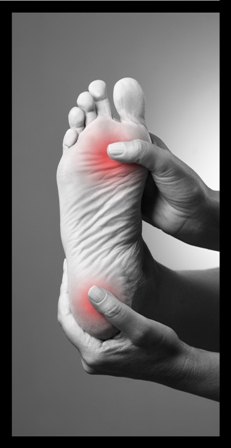

Heel Pain and Plantar Fasciitis

Plantar fasciitis is an inflammation of the plantar fascia of the foot and may be located at insertion into the calcaneus (heel bone) or under the arch.

This may be due to chronic (long term) repetitive stress or an acute injury which may lead to a partial rupture. If it is due to an acute injury there will be signs of bruising.